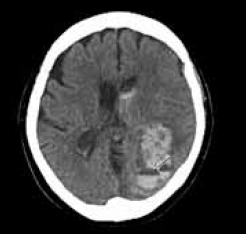

Homem de 52 anos, com histórico de hipertensão arterial sistêmica não aderente ao tratamento, apresenta-se no pronto-socorro com cefaleia súbita e intensa, acompanhada por vômitos e rápida deterioração do nível de consciência.

A tomografia computadorizada (TC) encontra-se a seguir.

Com base nos protocolos atuais para manejo avançado do acidente vascular cerebral hemorrágico (AVCH), das opções apresentadas, assinale a alternativa que melhor reflete a conduta terapêutica inicial mais adequada.